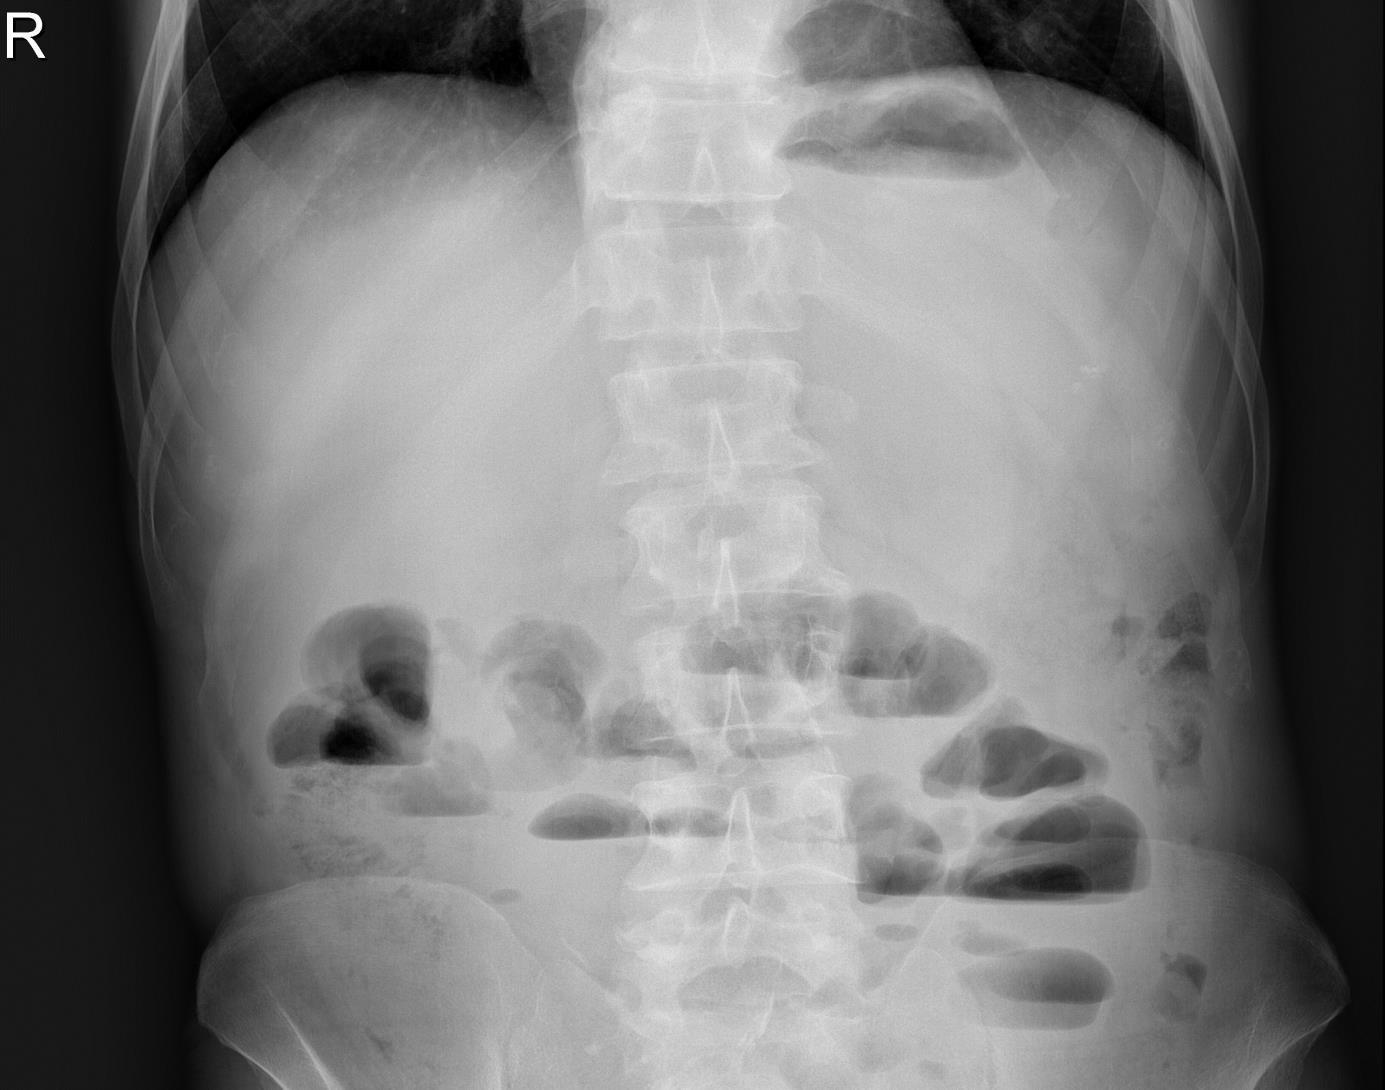

Badania rentgenowskie w diagnostyce bólów brzucha u dzieci często dają charakterystyczny obraz w poszczególnych schorzeniach. Objaw 'półksiężyca' (krzywoliniowa masa często spotykana blisko okrężnicy poprzecznej za zagięciem wątrobowym) charakterystyczny jest dla: